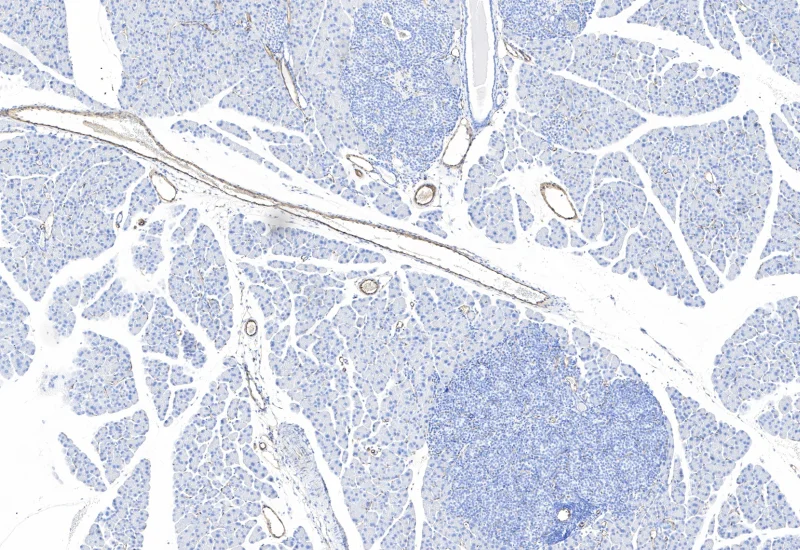

IHC Tumor Vascularization

Segment tissue into tumor and healthy/stromal regions, detect blood vessels (e.g., CD31), and quantify vessel number, area, density, and connectivity within each compartment.

The IHC Tumor Vascularization APP provides tissue detection including the separation into tumor tissue and healthy tissue (or tumor stroma). It additionally detects blood vessels based on appropriate stains (e.g. CD31) and measures number and area of the blood vessels. The vessel detection also can be set to close open stained vessel walls and to connect separated vessel sections within a definable distance. The APP outputs number and vessel density as well as areas of vessels, within tumor tissue and healthy tissue.

Original Image